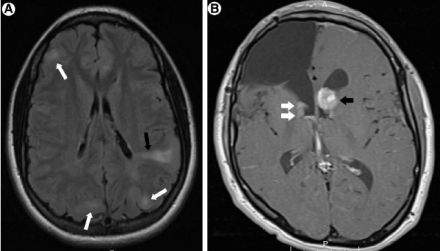

下图也是一个BHD病例,表现为肺部囊性病变+肾脏肿瘤+皮肤异常,提示我们一定鉴别TSC和BHD、要注意肺外表现。

图:BHD,肾透明细胞癌

TSC的肺部受累可以表现为LAM,这也是我们临床需要关注的,所以当诊断了患者LAM之后,也需要再进一步看看有没有TSC的临床表现。TSC是一种多系统遗传性、肿瘤性疾病,临床表现多样,除了LAM,还包括室管膜下巨细胞星形细胞瘤 (SEGA)、面部血管纤维瘤、肾血管肌脂瘤 (AML)等。

最后,了解一下Birt-Hogg-Dube综合征(BHD)。肺部囊性病变出现于90%的BHD患者(常具有气胸和/或家族史),是一种常染色体显性遗传疾病,多有家族史,通过FLCN基因突变能够明确诊断,也可伴有皮肤和肾脏肿瘤,需要仔细查看。